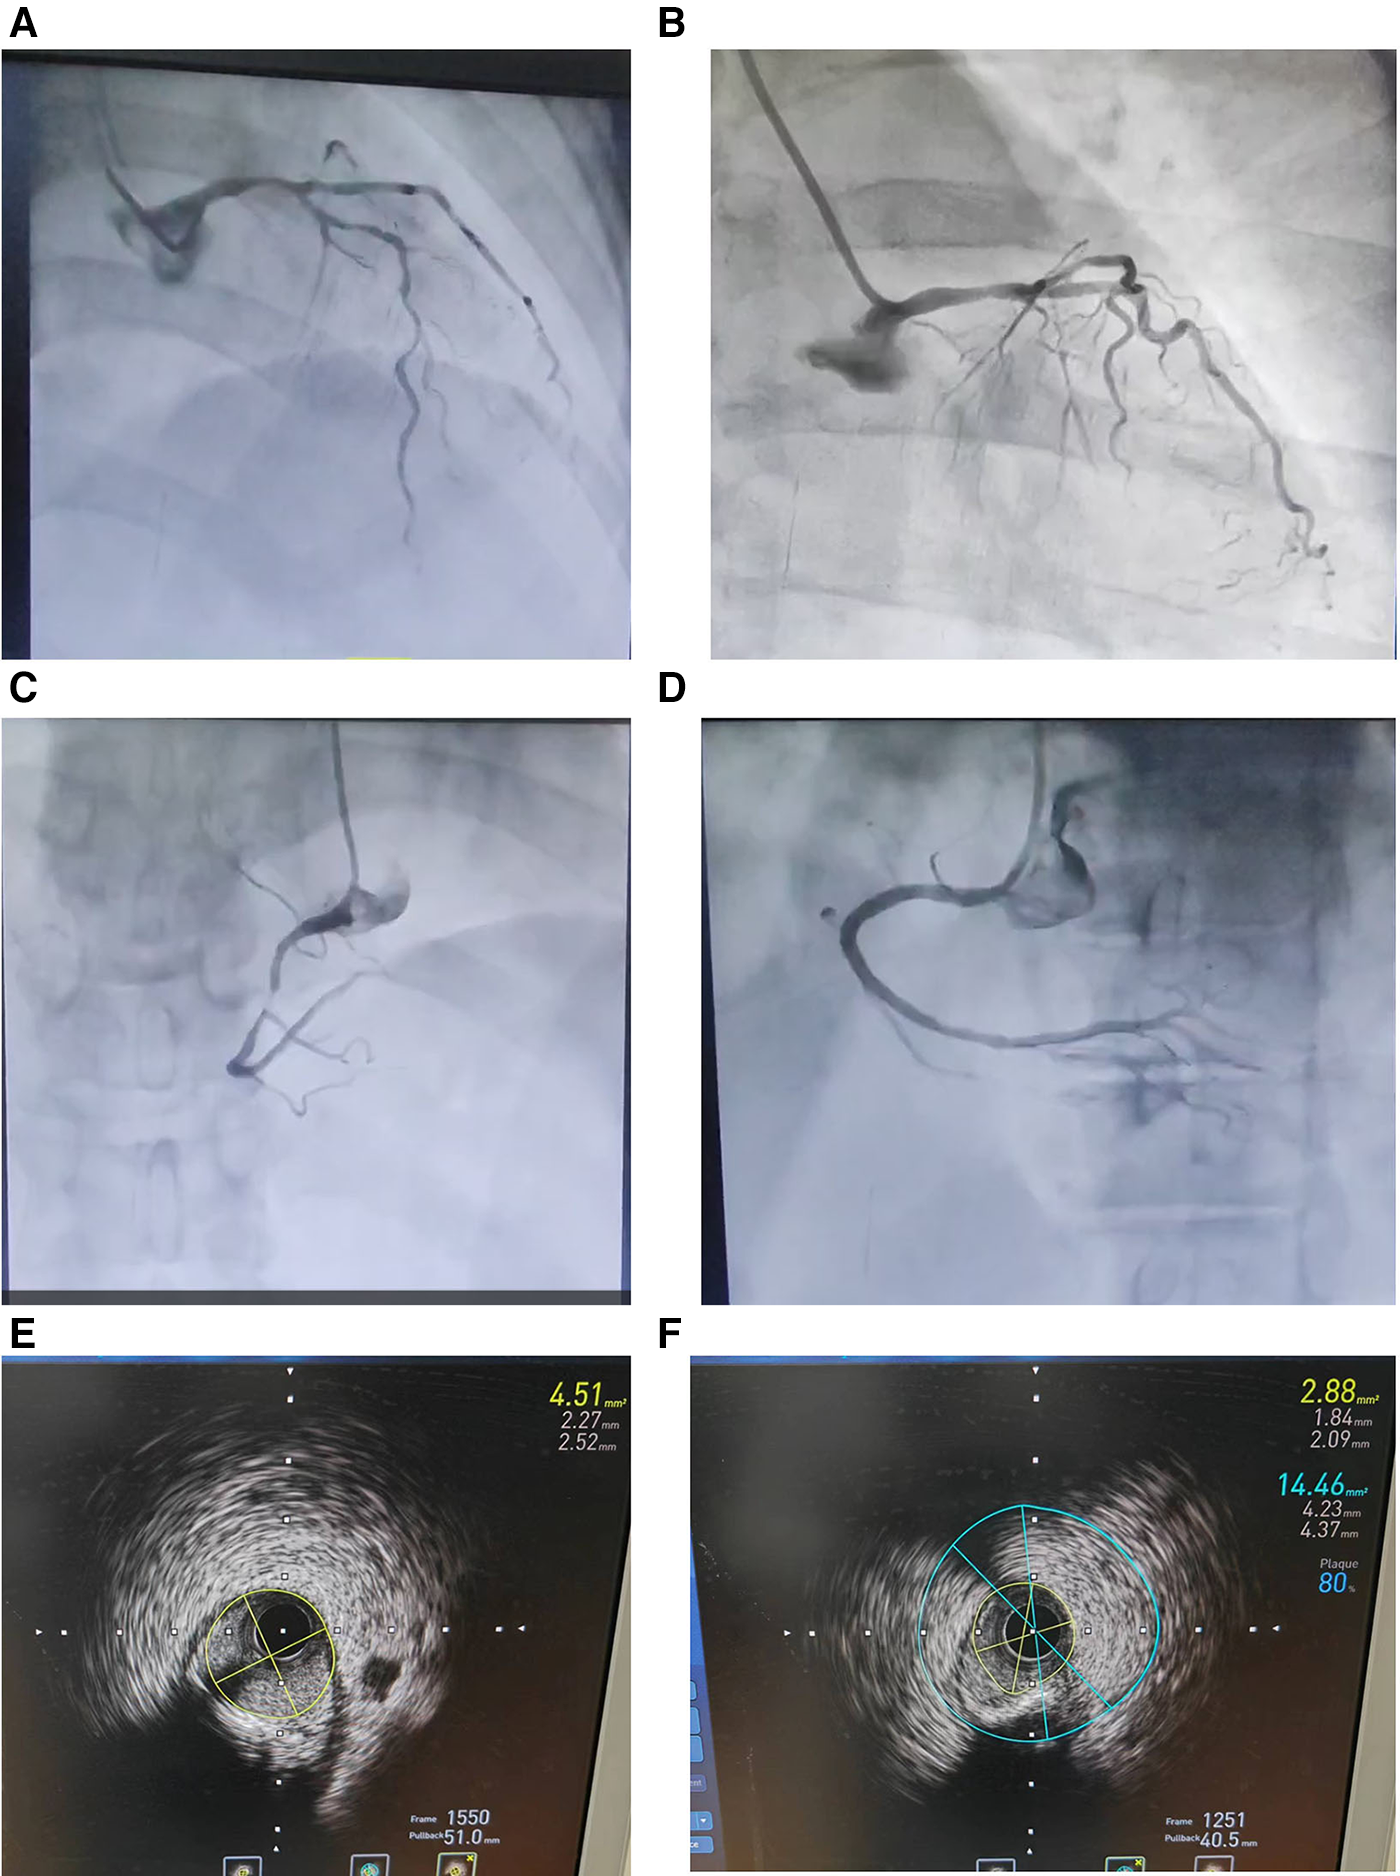

A 70-year-old female patient presented with paroxysmal exertional chest tightness persisting for one month, alleviated by a few minutes of rest. Forty years ago, the patient suffered from postpartum hemorrhage, without blood transfusion, subsequently developing lactation failure and amenorrhea. Five years later, she was diagnosed with SHS at the Affiliated Hospital of Shandong University. Management included 5 mg of prednisone acetate in the morning for secondary adrenal insufficiency, and 50 ug of levothyroxine for secondary hypothyroidism. Apart from medication adherence, the patient lacked awareness regarding adrenal insufficiency. The patient had a decade-long history of hypertension, controlled with 5 mg of telmisartan and 5 mg of amlodipine daily. This patient had a weight of 46 kl, a height of 1.57 m, and a BMI of 18.66 kg/m2. Upon hospital admission, her vital signs were stable with a blood pressure of 122/58 mmHg, and a heart rate of 65 beats per minute. Physical examination revealed no pulmonary rales, cardiac murmurs, lower limb edema. Laboratory finding indicated elevated blood troponin I (0.5487 ng/ml, 0–0.0175 ng/ml), normal blood sodium (141.5 mmol/L, 137 mmol/L–147 mmol/L), and elevated fasting total cholesterol (6.28 mmol/L, 3 mmol/L–5.7 mmol/L). Thyroid function tests revealed low level of free thyroxine (FT4) (6.77 pmol/L, 7.98 pmol/L–16.02 pmol/L), with normal levels of free triiodothyronine (FT3) and thyroid stimulating hormone. Electrocardiogram indicated sinus bradycardia. We diagnosed the patient with acute non-ST segment elevation myocardial infarction (NSTEMI) and performed percutaneous coronary angiography (CAG) and intravascular ultrasound (IVUS) examination. We found that the stenosis degree was 40%, 80%, and 60%, 98%, and almost completely occluded, respectively, in the left main trunk (LM), the proximal and middle segments of the left anterior descending branch (LAD), the proximal segments of the left circumflex branch (LCX), and the middle segment of the right coronary artery (RCA) (Figures 1A–C). The minimum lumen area at the distal stenosis of the LM was 4.51 mm2 (Figure 1E), the plaque load at the most severe stenosis of the proximal LAD was 80%, with a minimum lumen area of 2.88 mm2 (Figure 1F). Due to the patient's refusal to undergo coronary artery bypass grafting, two stents were inserted in the middle segment of the RCA (Figure 1D). The intervention lasted for 2 h, including coronary angiography, bilateral intravascular ultrasound examination, patient involvement in treatment decision-making based on examination results, and subsequent coronary intervention treatment, utilizing 130 ml of iodixanol. The patient did not experience any chest discomfort, but was nervous and had a blood pressure rise to 190/100 mmHg, managed with sublingual nifedipine tablets and intravenous isosorbide nitrate. Following percutaneous intervention (PCI), the patient experienced a sequence of symptoms from the 12th to the 50th h, including nausea and loss of appetite, profuse sweating, mild limb twitching, and drowsiness in sequence (Table 1). Limb twitching persisited for 18 h from the 38th to the 56th h post-PCI. On the 24th h post-PCI, the patient was diagnosed with hyponatremia (Table 1), and 2%−3% sodium chloride was intermittently administered intravenously. Despite increased sodium chloride supplementation, symptoms persisted until administration of hydrocortisone, leading to symptom resolution and rapid improvement in blood sodium levels (Table 1). By the 62nd h post-PCI, symptoms of hyponatremia completely resolved, with blood sodium level increasing from 114.2 mmol/L to 132 mmol/L (Table 1). At the 86th h post-PCI, blood sodium level returned to normal. After 40 h, blood tests revealed low levels of cortisol (2.76 ug/dl, 6.7ug/dl–22.6 ug/dl), ACTH (4.26 pg/ml, 10.1 pg/ml–57.6 pg/ml), FT3 (3.41 pmol/L, 3.53 pmol/L−7.37 pmol/L), and FT4 (7.12 pmol/L, 7.98 pmol/L–16.02 pmol/L). Following discharge, the patient continued oral medication with 2.5 mg prednisone acetate and 50 ug levothyroxine sodium daily, as well as dual antiplatelet drugs, statins, and antihypertensive agents. During the next nine-month follow-up period, the patient did not experience ischemic symptoms or hyponatremia.

Figure 1. Coronary angiography (A–D) and intravascular ultrasound examination (E and F) in an elderly patient with Sheehan's syndrome. (A) The stenosis degree is 40%, 80%, and 60%, respectively, at the end of the left main trunk, the proximal and middle segments of the left anterior descending branch. (B) The stenosis degree is 98% at the proximal segments of the left circumflex branch. (C) The stenosis degree is almost completely occluded at the middle segment of the right coronary artery. (D) Two stents are inserted in the middle segment of the RCA. (E) The minimum lumen area at the distal stenosis of the left main trunk is 4.51 mm2. (F) The plaque load at the most severe stenosis of the proximal left anterior descending branch is 80%, and the minimum lumen area is 2.88 mm2.